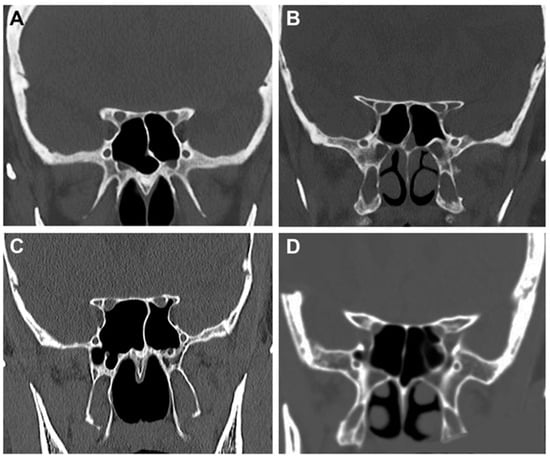

2.2. Radiological Study

3.2. Anatomo-Radiological Measurements